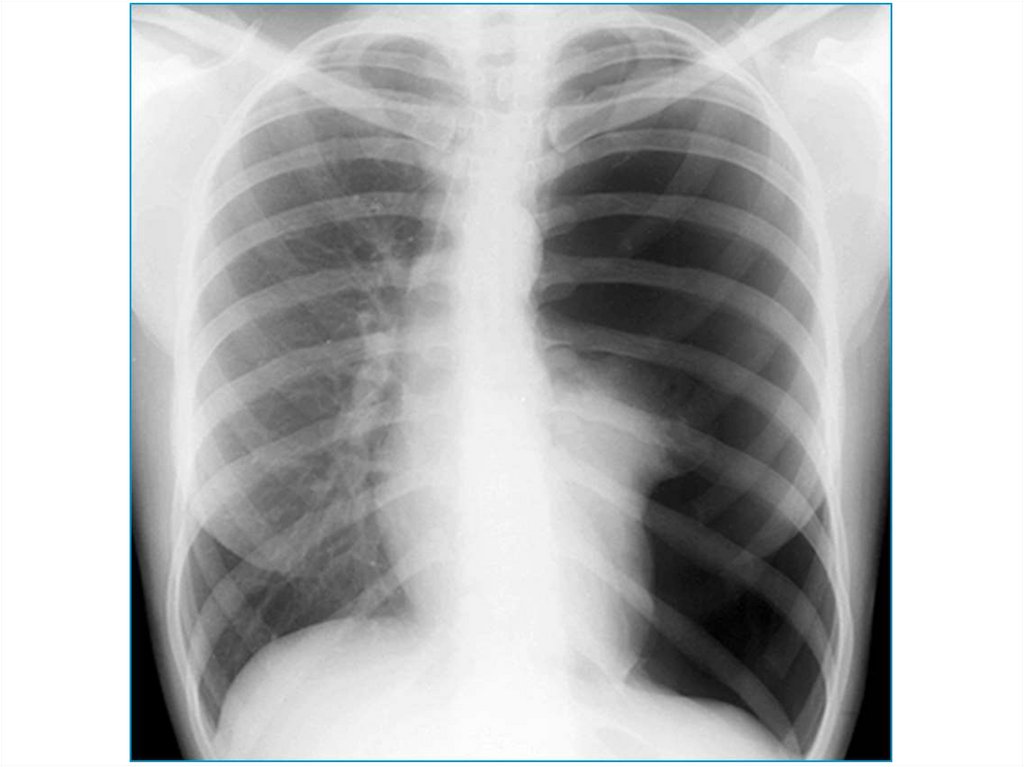

21. Обструкция бронха

Или обтурационная эмфизема, которая

развивается в результате бронхиальной астмы,

пневмонии, бронхита, бронхиолита,

пневмосклероза.

Видимая картина – тотальное одностороннее

просветление пораженного легкого.

23. Компенсаторная эмфизема

В случае ателектаза/удаления другого легкого.

Видимая картина – тотальное односторнее

просветление легкого, смещение средостения в

другую сторону.